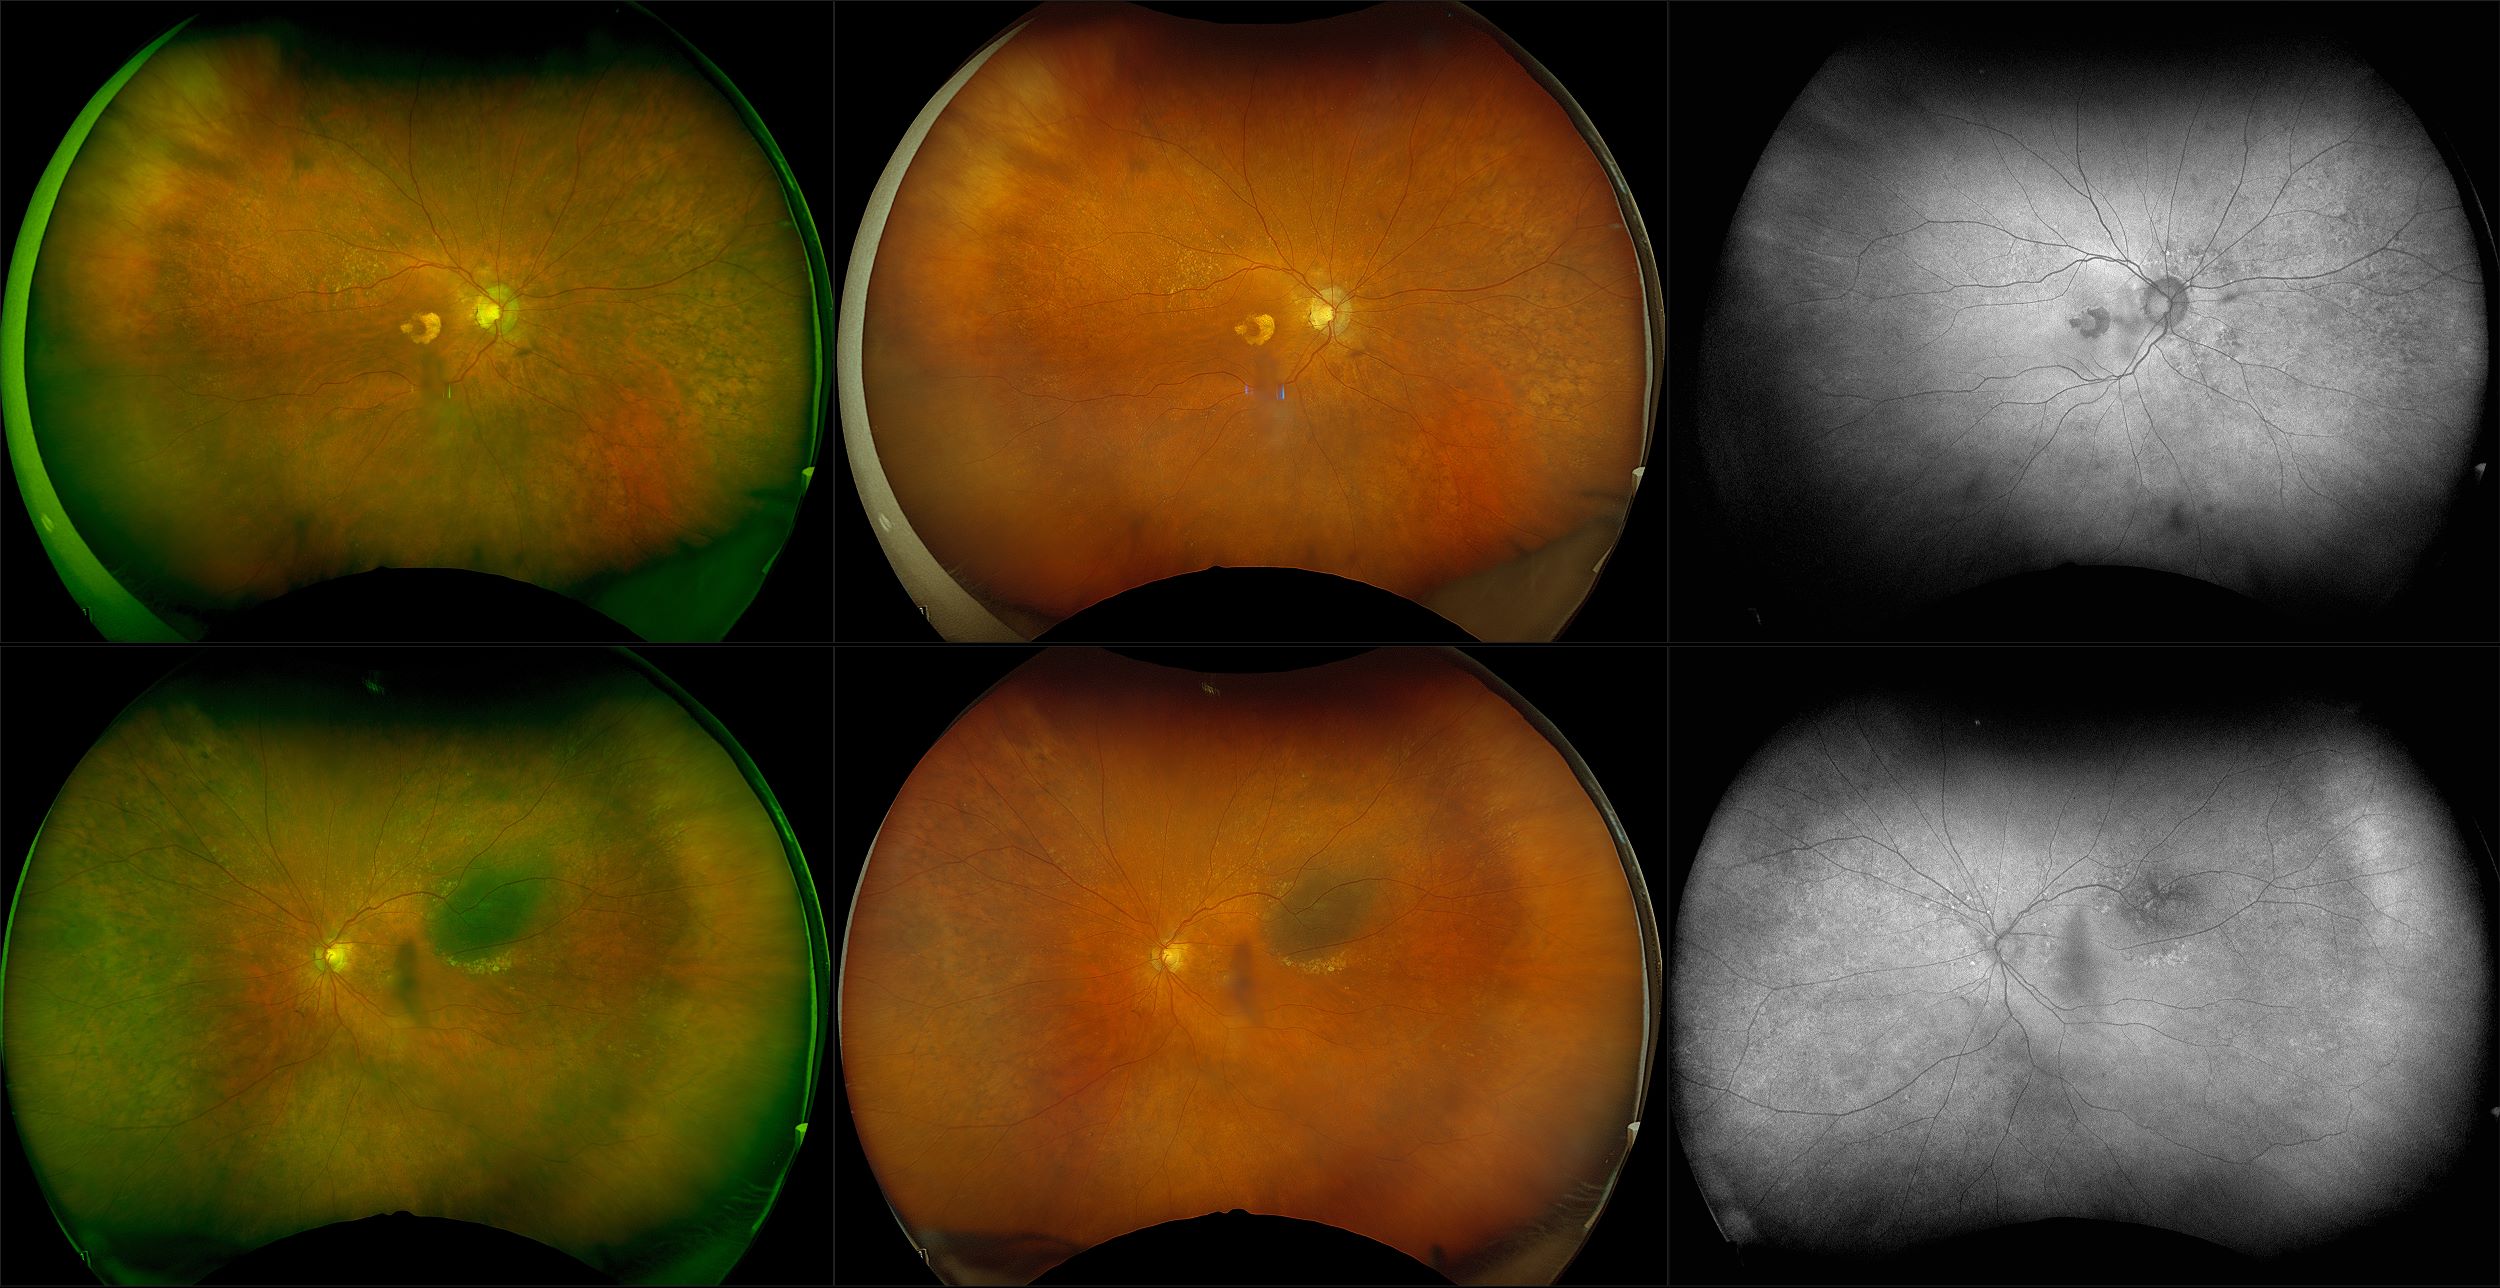

California - Choroidal Nevus, RG, AF

A choroidal nevus is simply an accumulation of melanocytes in the choroid. They are a space occupying mass or a benign melanoma. Choroidal nevi are slate gray in color, have indistinct margins, and may be slightly elevated (1-2 diopters). Since they are in the choroid, they are usually only seen in the red separation and not the green. The green separation may show the RPE degeneration associated with nevi which is seen as pigment mottling and drusen.